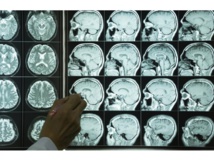

واكتشف الباحثون، في دراستهم التي نشرتها مجلة "ساينس أليرت" العلمية، وجود صلة بين انخفاض دخل الأسرة والتحلل السريع للمادة البيضاء داخل الأدمغة البشرية، لافتين إلى أن نتائج تحليلهم لمعطيات خاصة بعينة شملت 751 شخصا تتراوح أعمارهم بين 50 و91 عاما، وأخذت بعين الاعتبار عوامل مثل العمر والجنس وبعض المشكلات الصحية الرئيسية، توصلت إلى أن أولئك الذين ينتمون إلى الأسر الفقيرة أظهروا المزيد من علامات شيخوخة المادة البيضاء في أدمغتهم في فحوصات التصوير بالرنين المغناطيسي، وسجلوا درجات أقل في الاختبارات المعرفية من أولئك الذين يعيشون في الأسر الأكثر ثراء.

وذكروا أن هذه الدراسة هدفت إلى تقديم نظرة ثاقبة للمسارات التي تربط التعرضات الاجتماعية والاقتصادية "دخل الأسرة"، والمسارات الاجتماعية والاقتصادية لمسار الحياة مع البنية المجهرية للدماغ والأداء المعرفي في منتصف وأواخر مرحلة البلوغ، مؤكدين أن العيش في فقر والتعرض لـ "الحرمان الاجتماعي والاقتصادي المزمن" كان مرتبطا منذ فترة طويلة بسوء الحالة الصحية والتدهور المعرفي بشكل أسرع، بينما لم يكن لدى الأشخاص الذين ينتمون إلى دخل أسري مرتفع العلامات الخاصة بشيخوخة دماغ المادة البيضاء التي تأثير سلبي كبير على الأداء المعرفي.

يذكر أن المادة البيضاء، المسؤولة بشكل مباشر عن الشيخوخة، تعتبر ضرورية جدا عندما يتعلق الأمر بنقل الرسائل والإشارات حول الدماغ، ولكميتها المتوفرة نسبة من التأثير على القدرة الإدراكية.